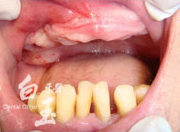

治療前